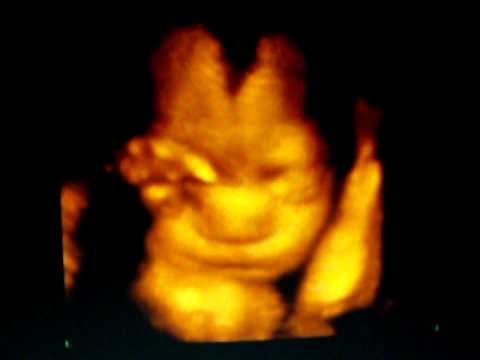

i had a 3d today and baby girl didn't wanna show her face, and the lady kept poking around and wiggling my belly like crazy! My baby girl just wanted to sleep....I'm mad at myself that I let her wiggle her around like that, I feel like a bad mom

! Anyone else have this happen?

However... This doesn't make you a bad mom!! Babies have a LOT of layers of protection in there, so I'm sure she is just fine!